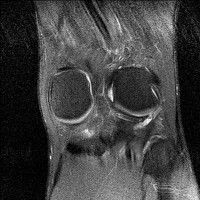

무릎 mri 간단히 봐주실 수 있으시나요 ㅠㅠ

안녕하세요 8년전 십자인대 수술하고 최근 무리한 운동에 무릎 불편감이 생겨서

mri 찍었습니다.

진단결과는 첫 찍은 병원에서 활액막염 이라는 진단을 받았습니다. 혹시 봐주실 수 있으실까요?

올라온 MRI가 단편적이라서 정확한 진단에 어려움이 있지만 십자인대에는 큰 이상이 있지는 않은것 같으며, 무릎관절내 물이 있는 것으로 보아 활액막염의 진단이 맞을 것 같습니다.

하지만 단편적인 영상이기 때문에 촬영병원에서 정확한 판독지 등을 받으시는 것이 좋겠습니다.